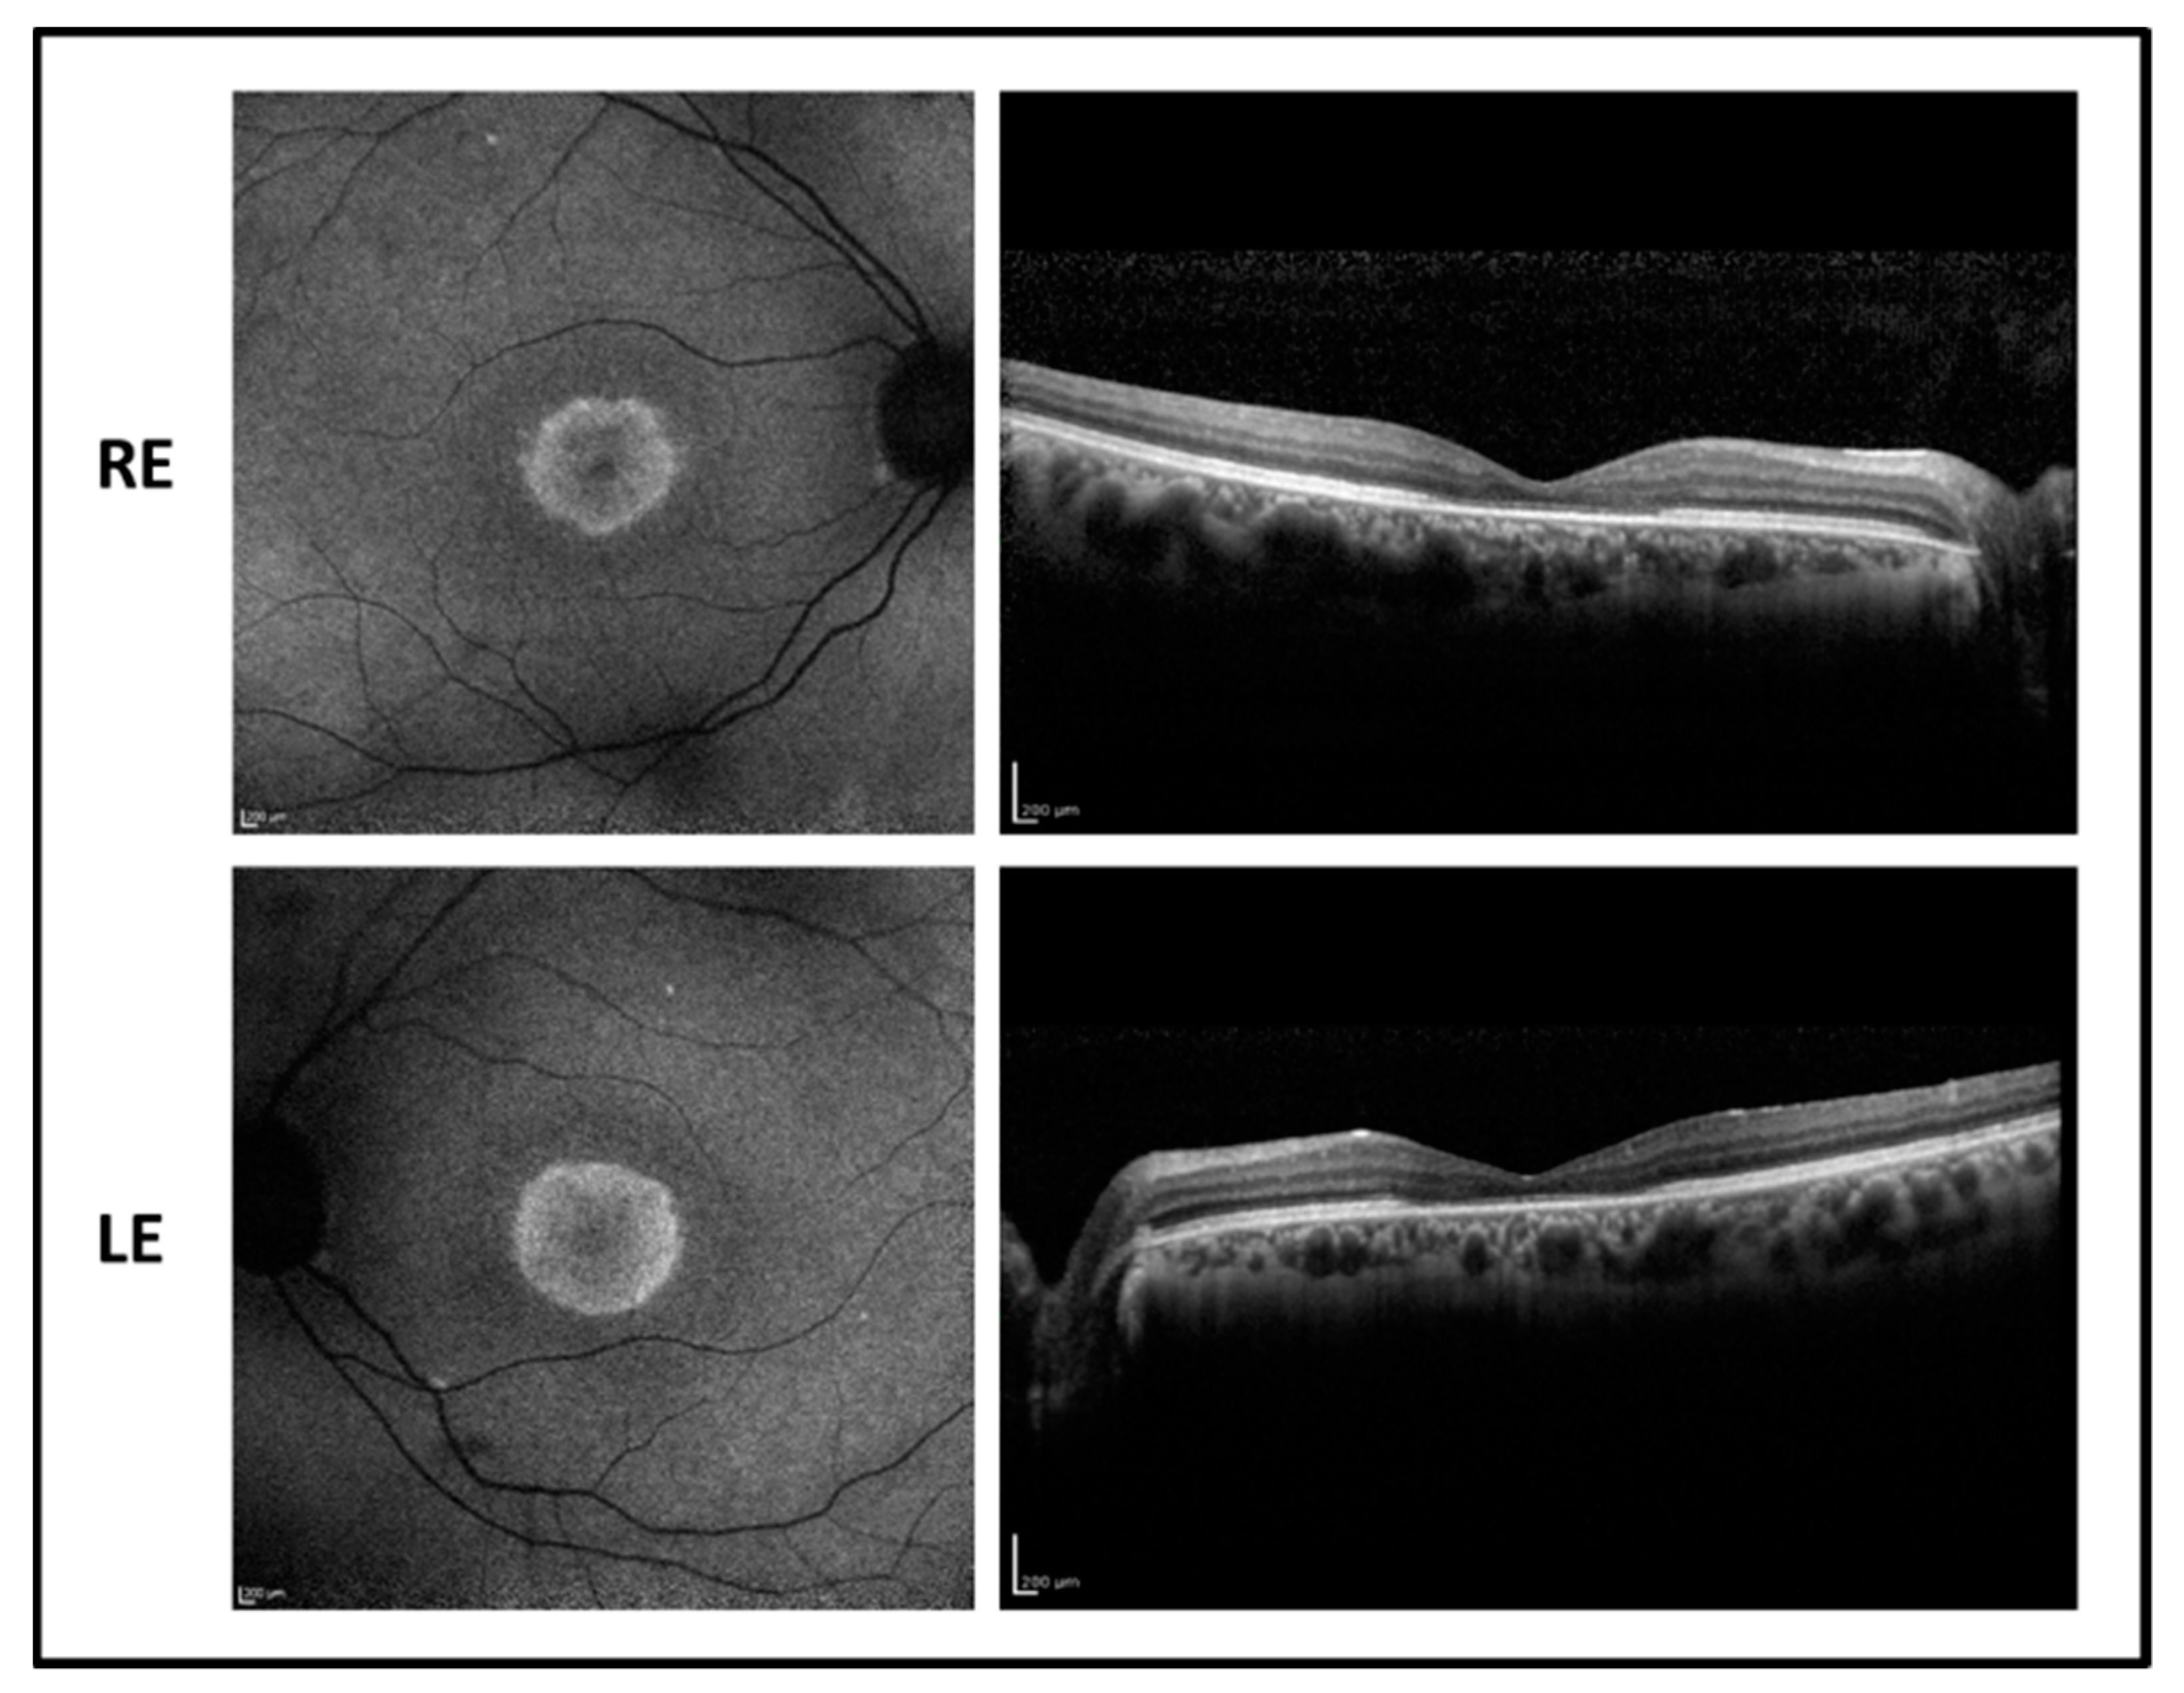

The fundus examination showed normal optic disk, signs of foveal atrophy, and “salt and pepper” peripheral retinopathy. Fundus autofluorescence revealed a dark central area due to the absence of the RPE surrounded by an unusual hyperfluorescent perifoveal ring in both eyes while infrared retinography showed foveal atrophy. OCT imaging revealed a marked reduction of the foveal thickness associated with a photoreceptor layer disruption (Figure 3). Goldmann visual field test showed central scotoma with a mild peripheral constriction.

Figure 3. Fundus autofluorescence (left side) and OCT (right side) images of the right eye (RE) and left eye (LE) of patient 2 showing central hypofluorescence with hyperfluorescent perifoveal ring and marked reduction of foveal thickness with photoreceptor defect.